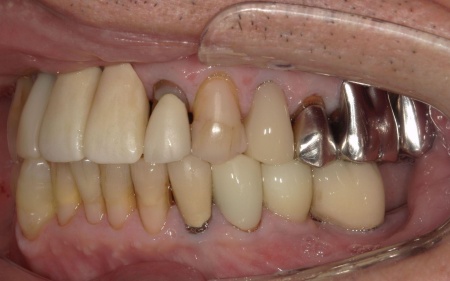

70代男性 右下奥歯を抜いてインプラント治療で噛み合わせを回復した症例

まずは投薬治療を行いましたが、症状の改善は見られませんでした。

患者様には「投薬で効果が見られない場合は抜歯が必要になる可能性がある」とお伝えしていたため、抜歯後にインプラント治療を行う提案をし、同意いただきました。

まず、右下奥歯(第2小臼歯)を抜き、骨が治癒するのを待ってから、インプラントを埋入します。

インプラントと顎の骨がしっかりと結合したら、精密な型取りを行い、インプラント上部に装着する最終的な被せ物を作製しました。

最後に完成した被せ物を装着し、見た目や噛み合わせに問題がないことを確認して、治療を終了しています。